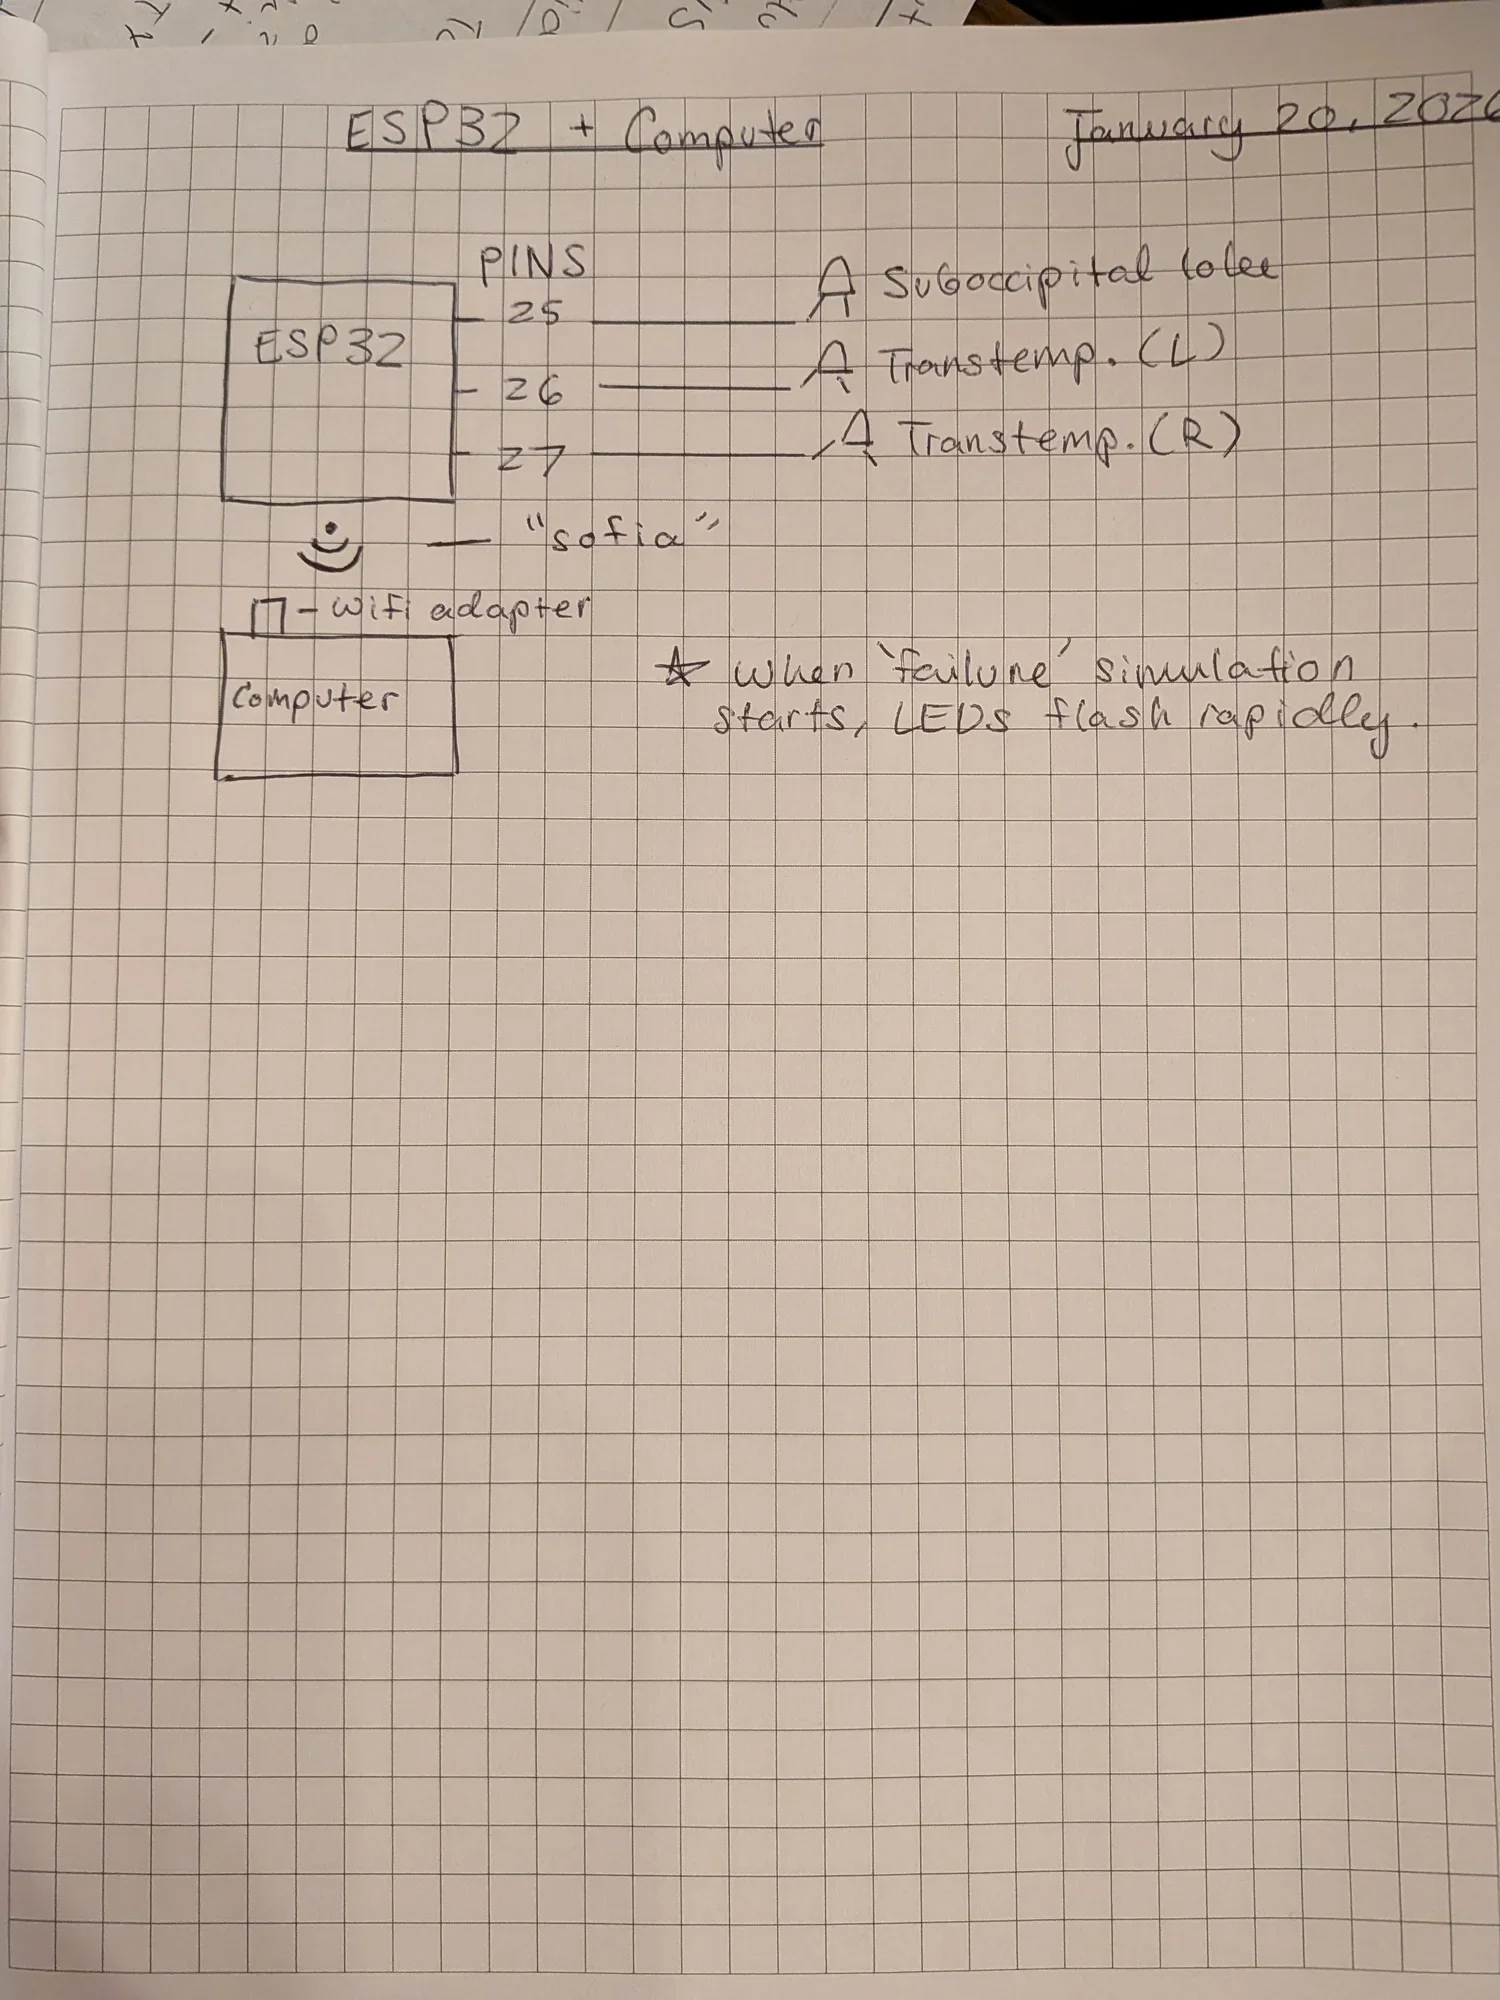

Design

To prove the concept of TONHI, we designed a prototype and wiring setup that will simulate rising intracranial pressure.

Technical Specifications

Transcranial Dopplers

Transcranial ultrasound dopplers will be placed at both transtemporal lobes and the suboccipital lobe of the patient to capture blood flow information and intracranial pressure.